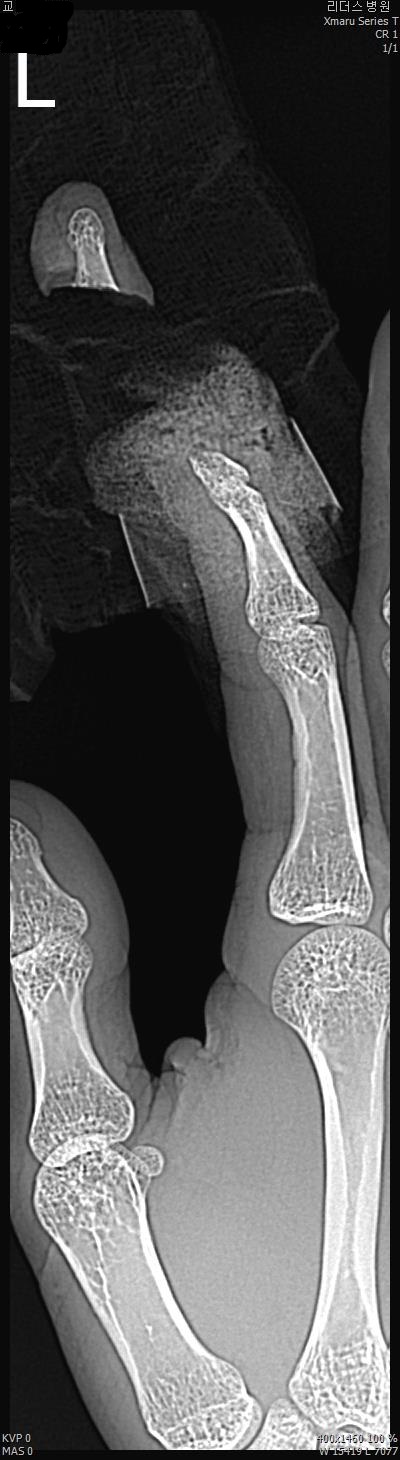

2017년 2월 14일 수지접합 ( 좌측 2수지 절단 치료 전, 후 모습)

2017년도 224일 당시 ( 외국인 교 **)께서 기계에 전달되어 본원 방문함.

올 해 19일 약 1년여간 수지접합 치료 전,후 과정을 올립니다.